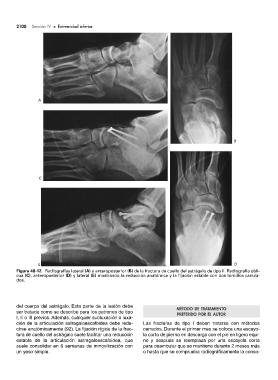

Figura 48-12. Radiografías lateral (A) y anteroposterior (B) de la fractura de cuello del astrágalo de tipo II. Radiografía obli-

cua (C), anteroposterior (D) y lateral (E) mostrando la reducción anatómica y la fijación estable con dos tornillos canula-

dos.